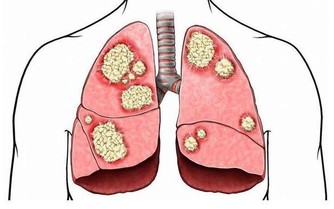

肝位於上腹部,肝癌初期並無徵兆,一般人難以察覺,

甚至當腫瘤增大至十公分以上時,有的人還是缺乏典型症狀。

當肝臟腫瘤逐步增大,有可能會壓迫附近的橫膈膜,亦可壓著肺部以下的肌肉神經。

肝癌在早期是沒有症狀的,往往發現為時已晚。